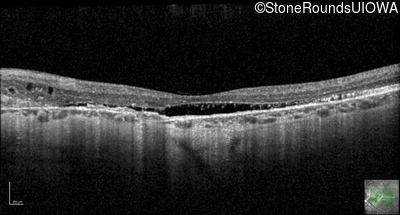

Optical Coherence Tomography - Left - 20/30 -2 sc

Exemplar / OCT Stack

OCT Stack